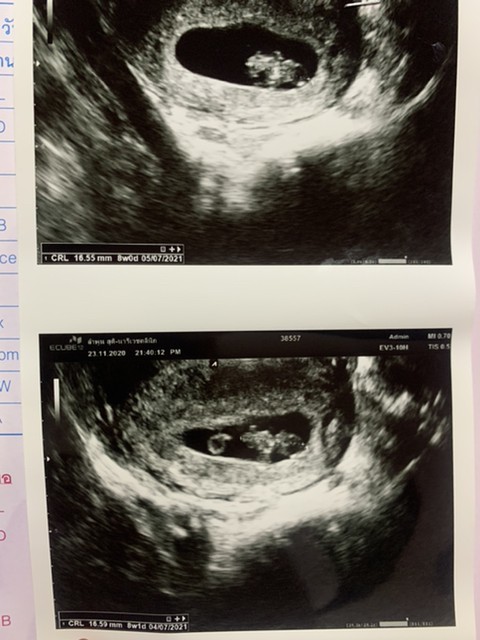

8มิ.ย64จ้า 10วีค